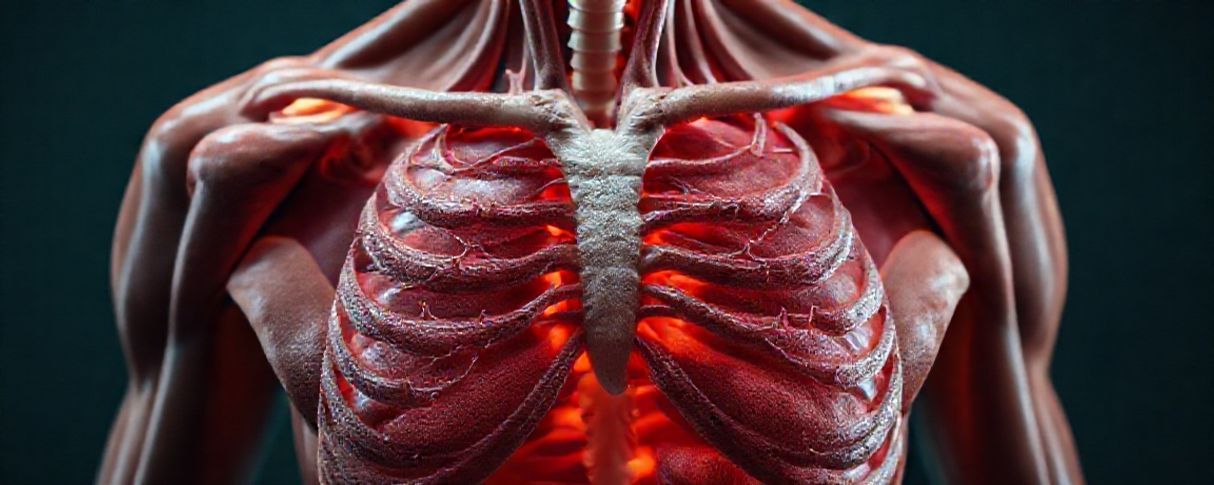

Problemas cardíacos também podem surgir, como palpitações e arritmias. O magnésio é essencial para o funcionamento correto do coração, ajudando a manter o ritmo regular dos batimentos. Quando está em falta, o risco de alterações no ritmo cardíaco aumenta.

Além disso, a deficiência pode causar formigamento e dormência nas mãos e pés. Isso acontece porque o magnésio participa da transmissão dos impulsos nervosos, e sua ausência prejudica essa função. Em casos mais graves, podem ocorrer convulsões e espasmos musculares intensos.